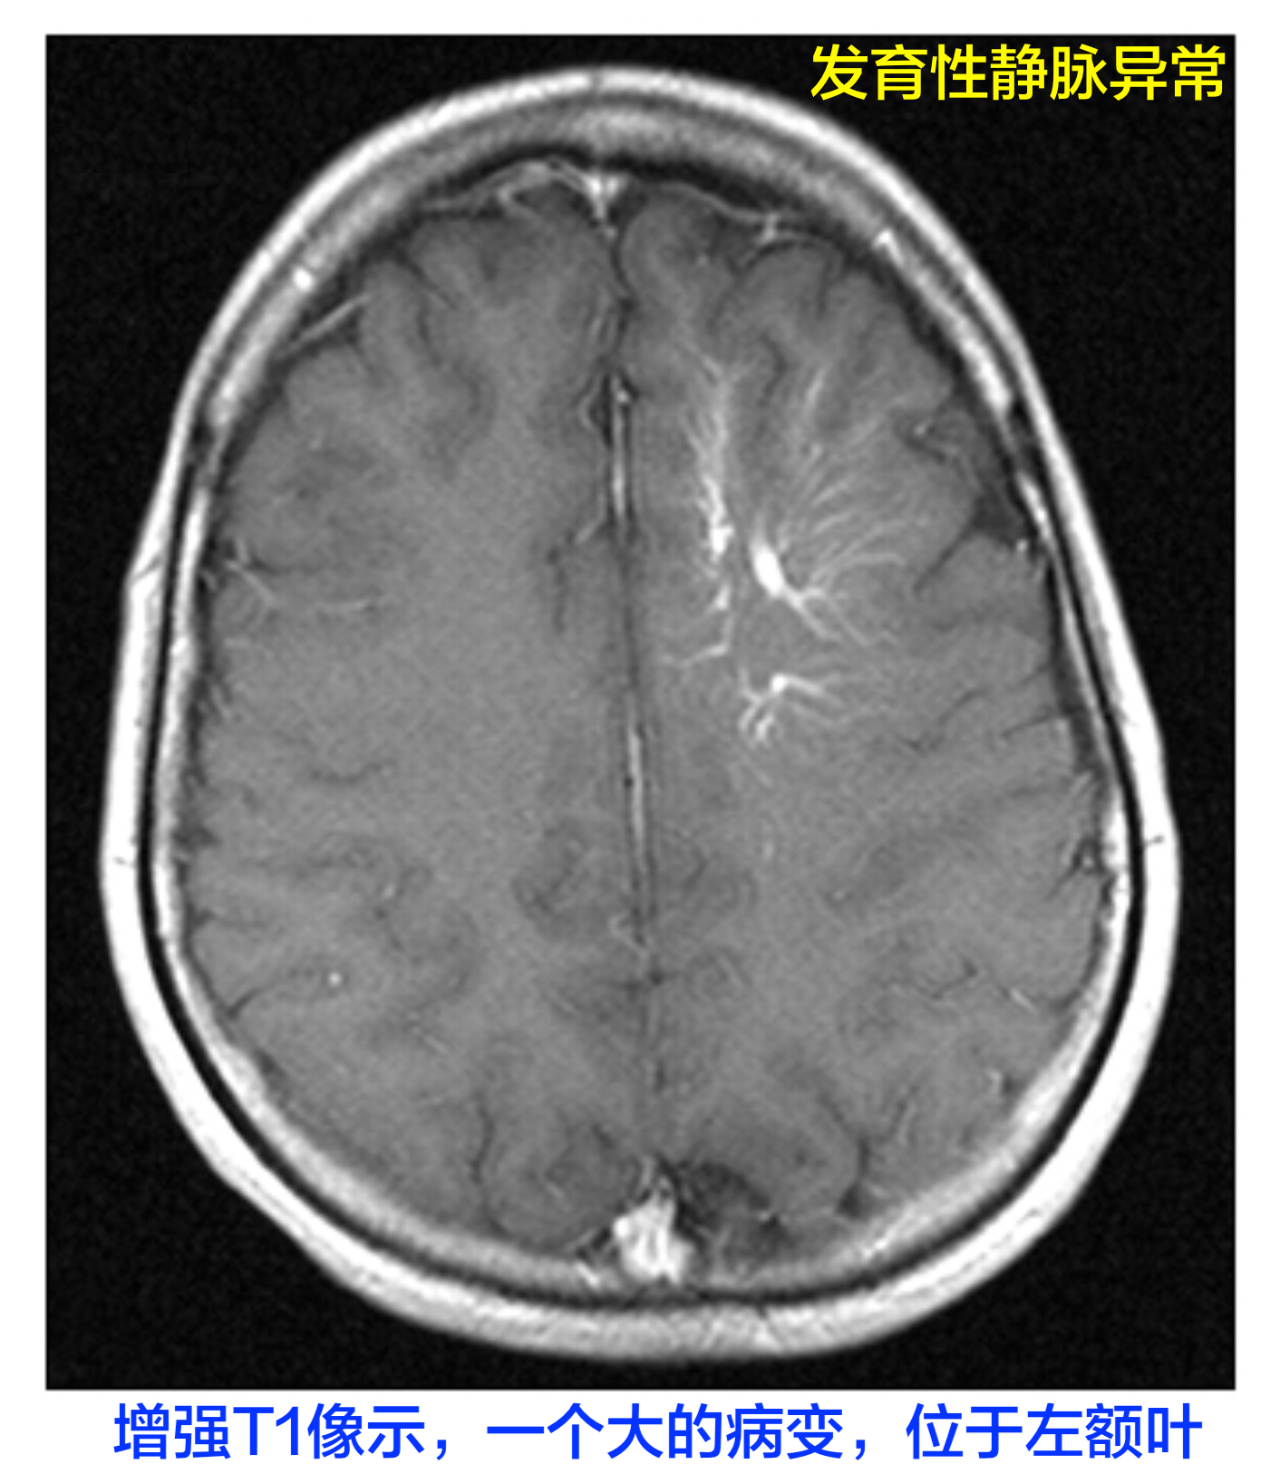

诊断虽然脑血管造影是诊断发育性静脉异常的金标准,但增强的CT、MRI和MRA检查,常可发现发育性静脉异常。在增强MRI-T1像上可见特征性的“日光照射”征,见下图:

对于不典型的病例,血管造影结果具有诊断意义:在毛细血管或静脉晚期相中,病变区域缺少正常的静脉,放射状排列的小髓静脉呈现特征性“海蛇头征”。